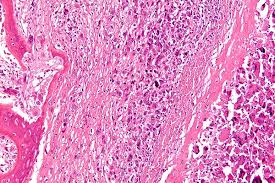

What Are The Signs Of Secondary Bone Cancer : Metastatic Bone Disease Fact Sheet Westmead Breast Cancer Institute - There is a persistent pain in the these signs and symptoms of secondary bone cancer occur very commonly.. This unusual kind of cancer affects both adults and children. In fact, benign (noncancerous) bone tumors are more common than malignant ones. This is cancer while starts in another organ of your body but has spread to the bones. In addition, cancers can also develop from bone marrow, the inner part of the bone that produces blood cells. Bone cancer starts in the cells of the bone or cartilage.

Bone Cancer Types Causes Symptoms from i0.wp.com A patient may also experience a pathological fracture as the first sign of bone cancer. People who have undergone bone marrow transplantation may also be at higher risk of developing bone cancer. There are several kinds of tumors that can grow in bones; The three major symptoms of secondary bone cancer that occur during the initial stages are: What is a secondary bone cancer? Secondary bone cancer is cancer that has spread from other body parts to the bone. Cancer in your bones usually started elsewhere in your body. Secondary bone cancer is much more common than primary bone cancer, but it's not considered bone secondary bone cancer is considered serious and classified as stage 4 (metastatic) disease since what is the risk of uterine cancer?

10 signs of bone cancerbone cancer is a malignant form of cancer that begins in the bone and destroys normal bone cells. Learn about bone cancer symptoms and treatments. It is difficult to cope with a diagnosis of secondary cancer but understanding more about it and the treatment you might have. Bone cancers are rare, and usually, they affect children than adults. Primary bone cancer is a rare type of cancer that begins in the bones. Nerve pain can be difficult to describe to a physician because it is unlike the usual types of pain. It's when a cancer that started somewhere else in the body has spread to the bones. While it's highly unlikely to be the result of bone cancer, it does require further. The decision to use surgery, chemotherapy or radiation therapy. Pain is the most common sign of bone cancer, and may become more noticeable as the tumor grows. Around 550 new cases are diagnosed each year in the uk. Learn more about these partnerships and how you too can join us in our. Fractures caused as a result of secondary bone cancer are called pathologic fractures.

Secondary Breast Cancer In The Bone from i.ytimg.com Primary bone cancers account for less than 1% of all cancers. It's when a cancer that started somewhere else in the body has spread to the bones. Secondary bone cancer occurs when cancers that develop elsewhere spread the outlook for a person with malignant bone cancer depends mainly on whether it has spread to other parts of the body. If you notice any of these symptoms, see your doctor. Bone cancer starts in the cells of the bone or cartilage. Cancer in your bones usually started elsewhere in your body. Fractures caused as a result of secondary bone cancer are called pathologic fractures. Read about bone cancer prognosis, treatment, symptoms, signs, survival rate, types, metastatic, and stage 4.

It is also called primary bone cancer. Bone cancer can either start in the cells of the bone (called primary bone cancer) or elsewhere in the body and spread to the bone (called secondary or metastatic there are three kinds of primary bone cancer : Most people who have a disease in their bones develop it from the secondary spread of another cancer. It's when a cancer that started somewhere else in the body has spread to the bones. Where the cancer first started is called the primary cancer. It may also be called metastatic bone cancer, bone metastases or bone mets. A patient may also experience a pathological fracture as the first sign of bone cancer. When bone cancer affects the nerves inside the bone, individuals describe a tingling, numb, or burning sensation. Learn more about these partnerships and how you too can join us in our. What are the signs and symptoms of bone cancer? Signs and symptoms of bone cancer include:bone pain.swelling and tenderness near the affected area.weakened bone, leading to fracture.fatigue.unintended. Not all bone tumors are malignant. Primary cancer of breast, prostate, lung, thyroid and renal spread to distant bone through blood or lymphatics.